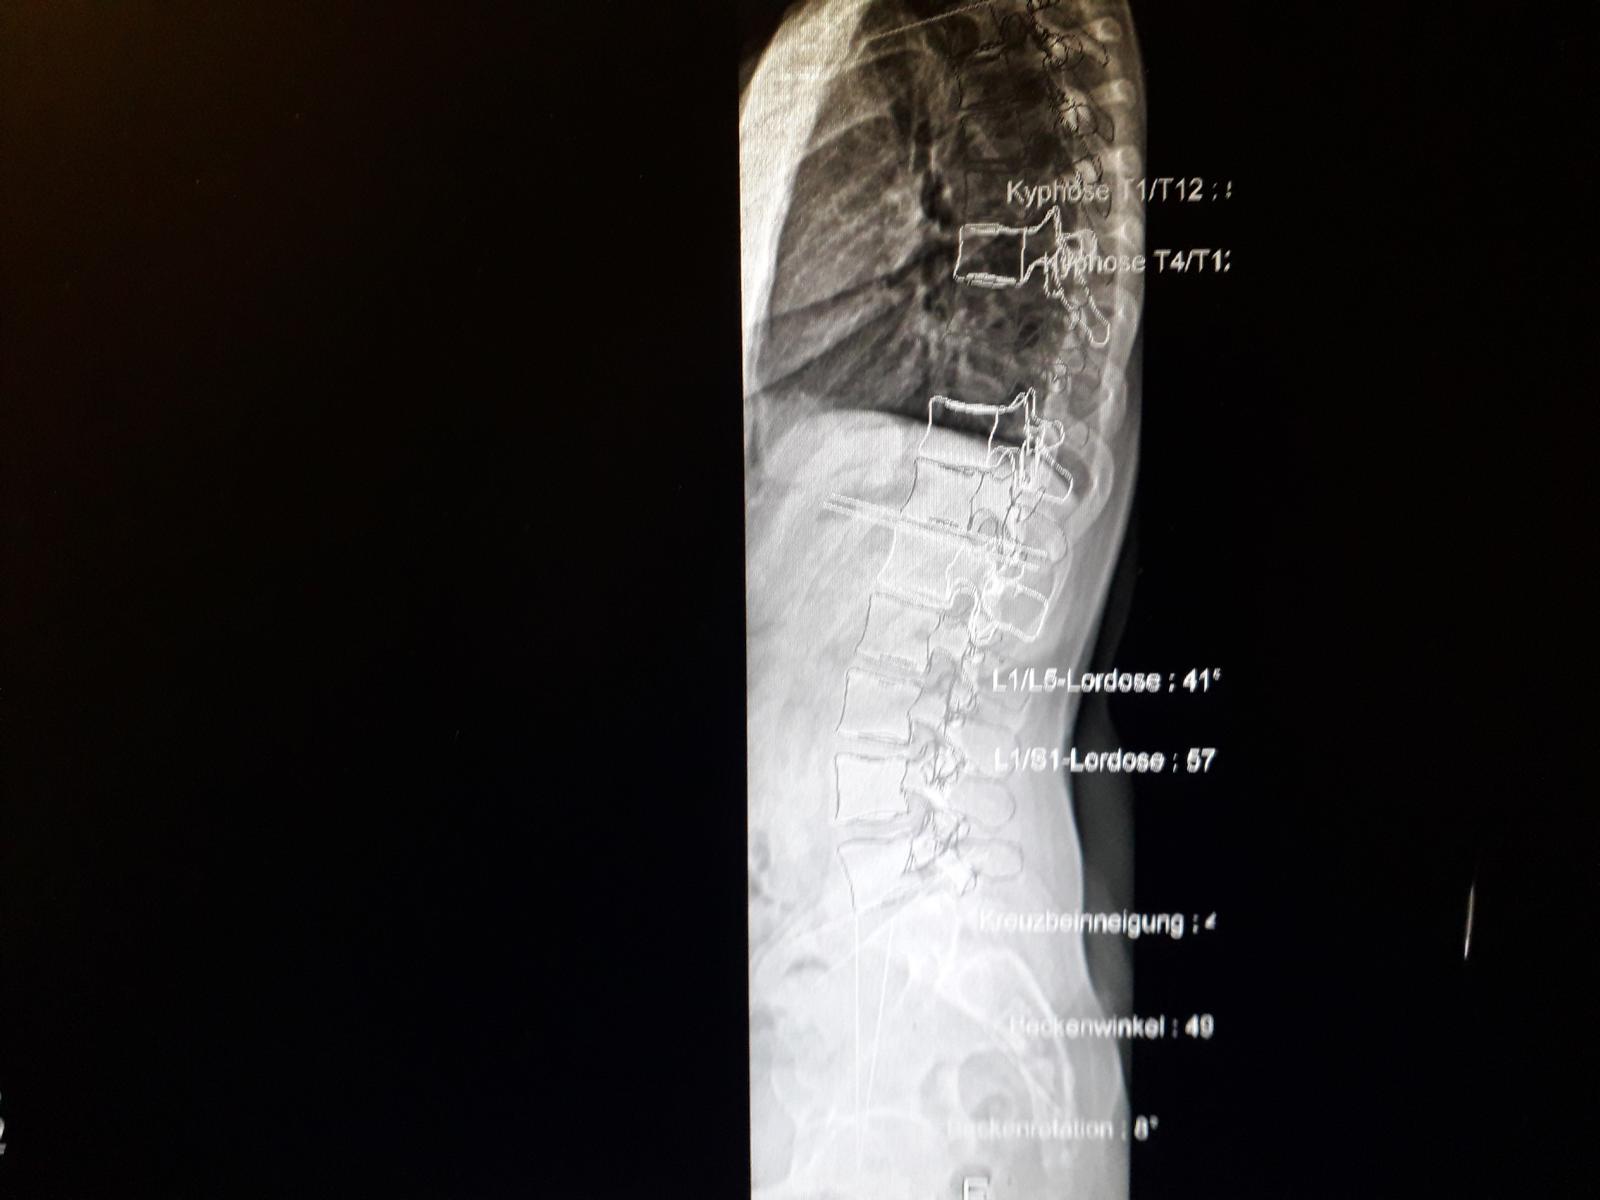

anbei 2 Bilder aus der Dateienreihe, wobei auf einem diesmal auch die BWS-Werte am Rand erkennbar sein müssten. Habe in erster Linie den oberen Bereich abfotografiert, da man diesen nicht mehr richtig erkennen kann, wenn ich versuche, die ganze Wirbelsäulenaufnahme auf einem Bild darzustellen.

Teilwirbelsäulenbild 1.JPG

(74.01 KiB) Noch nie heruntergeladen

Teilwirbelsäulenbild 2.JPG

(111.03 KiB) Noch nie heruntergeladen

Aber anhand des Teilwirbelsäulenbildes 1 wird jetzt klar, dass die Kyphose deutlich höher liegt, als normal. Als Vergleich habe ich eine entsprechende Grafik angefügt. Diese könntest Du neben Deine "gebastelte" verbesserte Gesamtaufnahme legen und Dir auch vorstellen, welche Korrektur bzw. Korrekturbewegung erforderlich ist. Möglicherweise ist das der Grund, warum die Therapeuten diese Kombination gegen Flachrücken/Rundrücken gewählt haben. Man muss direkt sehen und auch fühlen, was da durch was wie passiert. ;)